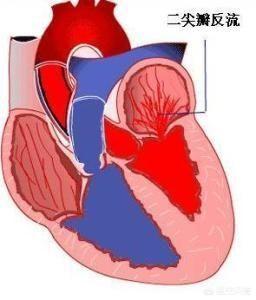

正常的心脏有四个“房间”,分别是左心房、左心室、右心房、右心室,相同一侧的心房和心室之间有瓣膜,我们可以把它理解成一扇门,左心房和左心室之间的门就是二尖瓣,右心房和右心室之间的门就是三尖瓣。剩余的两个瓣膜分别是主动脉瓣和肺动脉瓣,主动脉瓣位于左心室和主动脉之间,肺动脉瓣位于右心室和肺动脉之间。

当左心室舒张时,二尖瓣开放,血液从左心房流向左心室,当左心室收缩时,二尖瓣关闭,阻止血液返流,血液全部泵入主动脉供应全身。但是,受到诸多因素的影响,二尖瓣闭合不全,在左心室收缩期,血液从左心室返流到左心房,这种现象叫二尖瓣返流。

三尖瓣返流和二尖瓣返流的原理相似。在右心室舒张时,三尖瓣开放,血液从右心房流向右心室,当右心室收缩时,三尖瓣关闭,血液摄入大肺动脉,肺动脉血液经过循环滤过,将含氧量较低的静脉血过滤为含氧量较高、含二氧化碳较低的动脉血,之后血液经过肺静脉回流入左心房。受到诸多因素的影响,三尖瓣关闭不全,导致血液在右心室收缩期返流到右心房。我们把这种现象称为三尖瓣返流。

大家看一下面这个图片,记住二尖瓣三尖瓣的位置